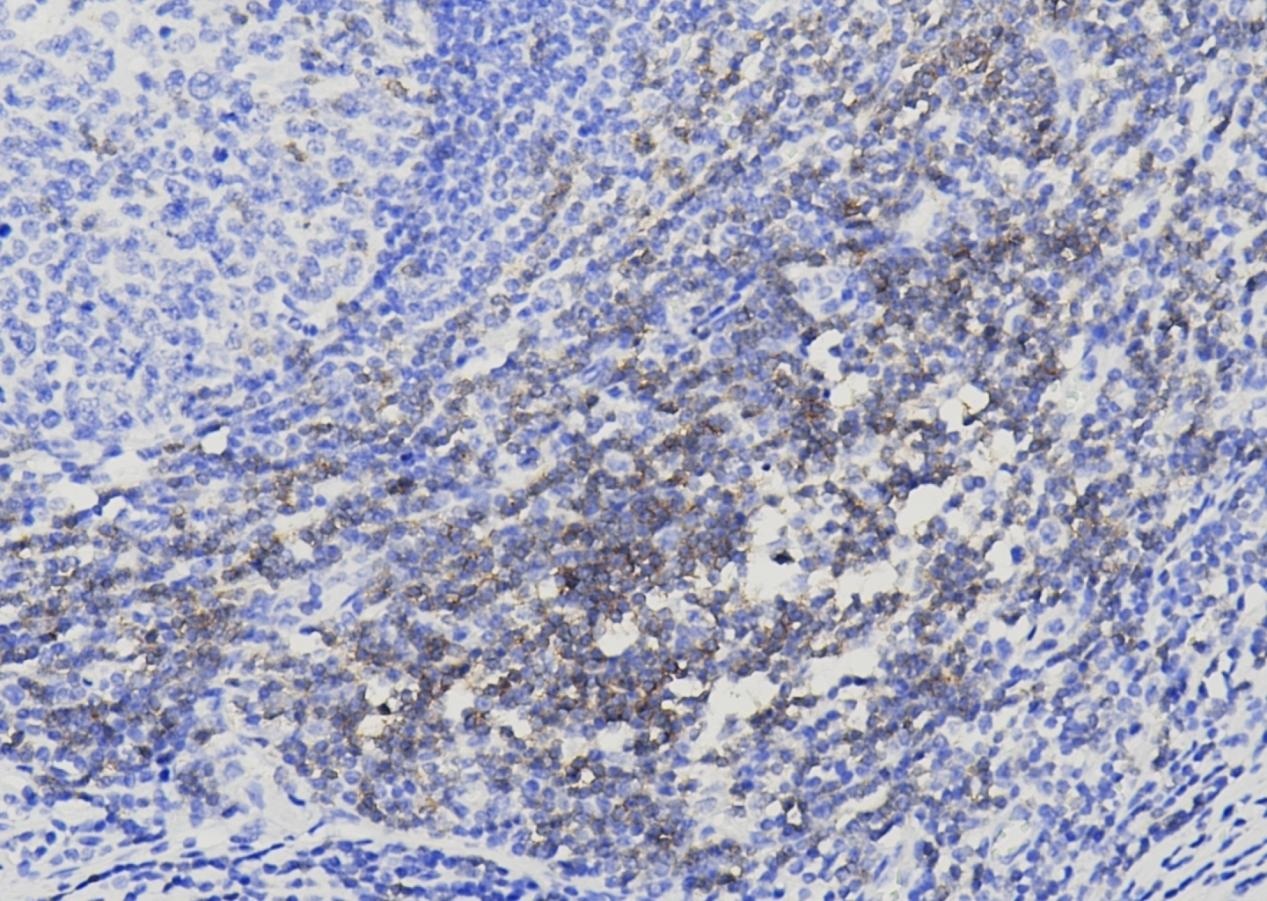

CD3

CD3分子是由五条肽链(y、δ、ε、ξ、n)以非共价键组成的复合分子,为T细胞抗原,是目前认为最能代表T细胞的标记抗体。CD3可与由a/β或γ/8组成的异源二聚体(TCR)形成复合受体分子,是T细胞识别抗原的主 要单位,具有稳定TCR结构和传递活化信号的作用。其表达于胸腺细胞、静止期T细胞和活化T细胞,是胸腺细胞、T淋巴细胞的标记物。CD3可用于瘤性和非瘤性的T淋巴细胞以及NK细胞的诊断。